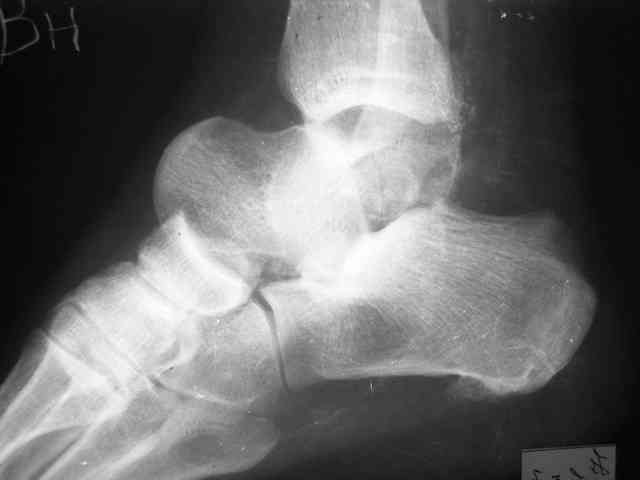

Уважаемый Александр! Как обещал представляю Р-граммы и операционные фото.

Можно убрать таранную кость, и поместить в образовавшуюся полость либо бусы из цемента с антибиотиками, либо вылепленный прямо по форме тарана спейсер. Целесообразность этого будет определяться распространенностью гнойного процесса. Может быть, будет достаточно только удаления тарана.

Вместе с аваскулярным куском кости устранится субстрат. Надо опасаться не мягких тканей, а плохо кровоснабжаемых. Если после удаления тарана добиться контакта хорошо васкуляризованных пятки и больщшеберцовой, мягкие ткани не давить, чтобы некроза раны не было, то все должно зажить.

Стабильность дает возможность расти сосудам. При хорошем кровоснабжении смежных фрагментов это все, что надо. А здесь есть большой секвестр. Разумно ли ждать, пока он васкуляризуется? Очевидно, без некрэктомии проблему не решить.